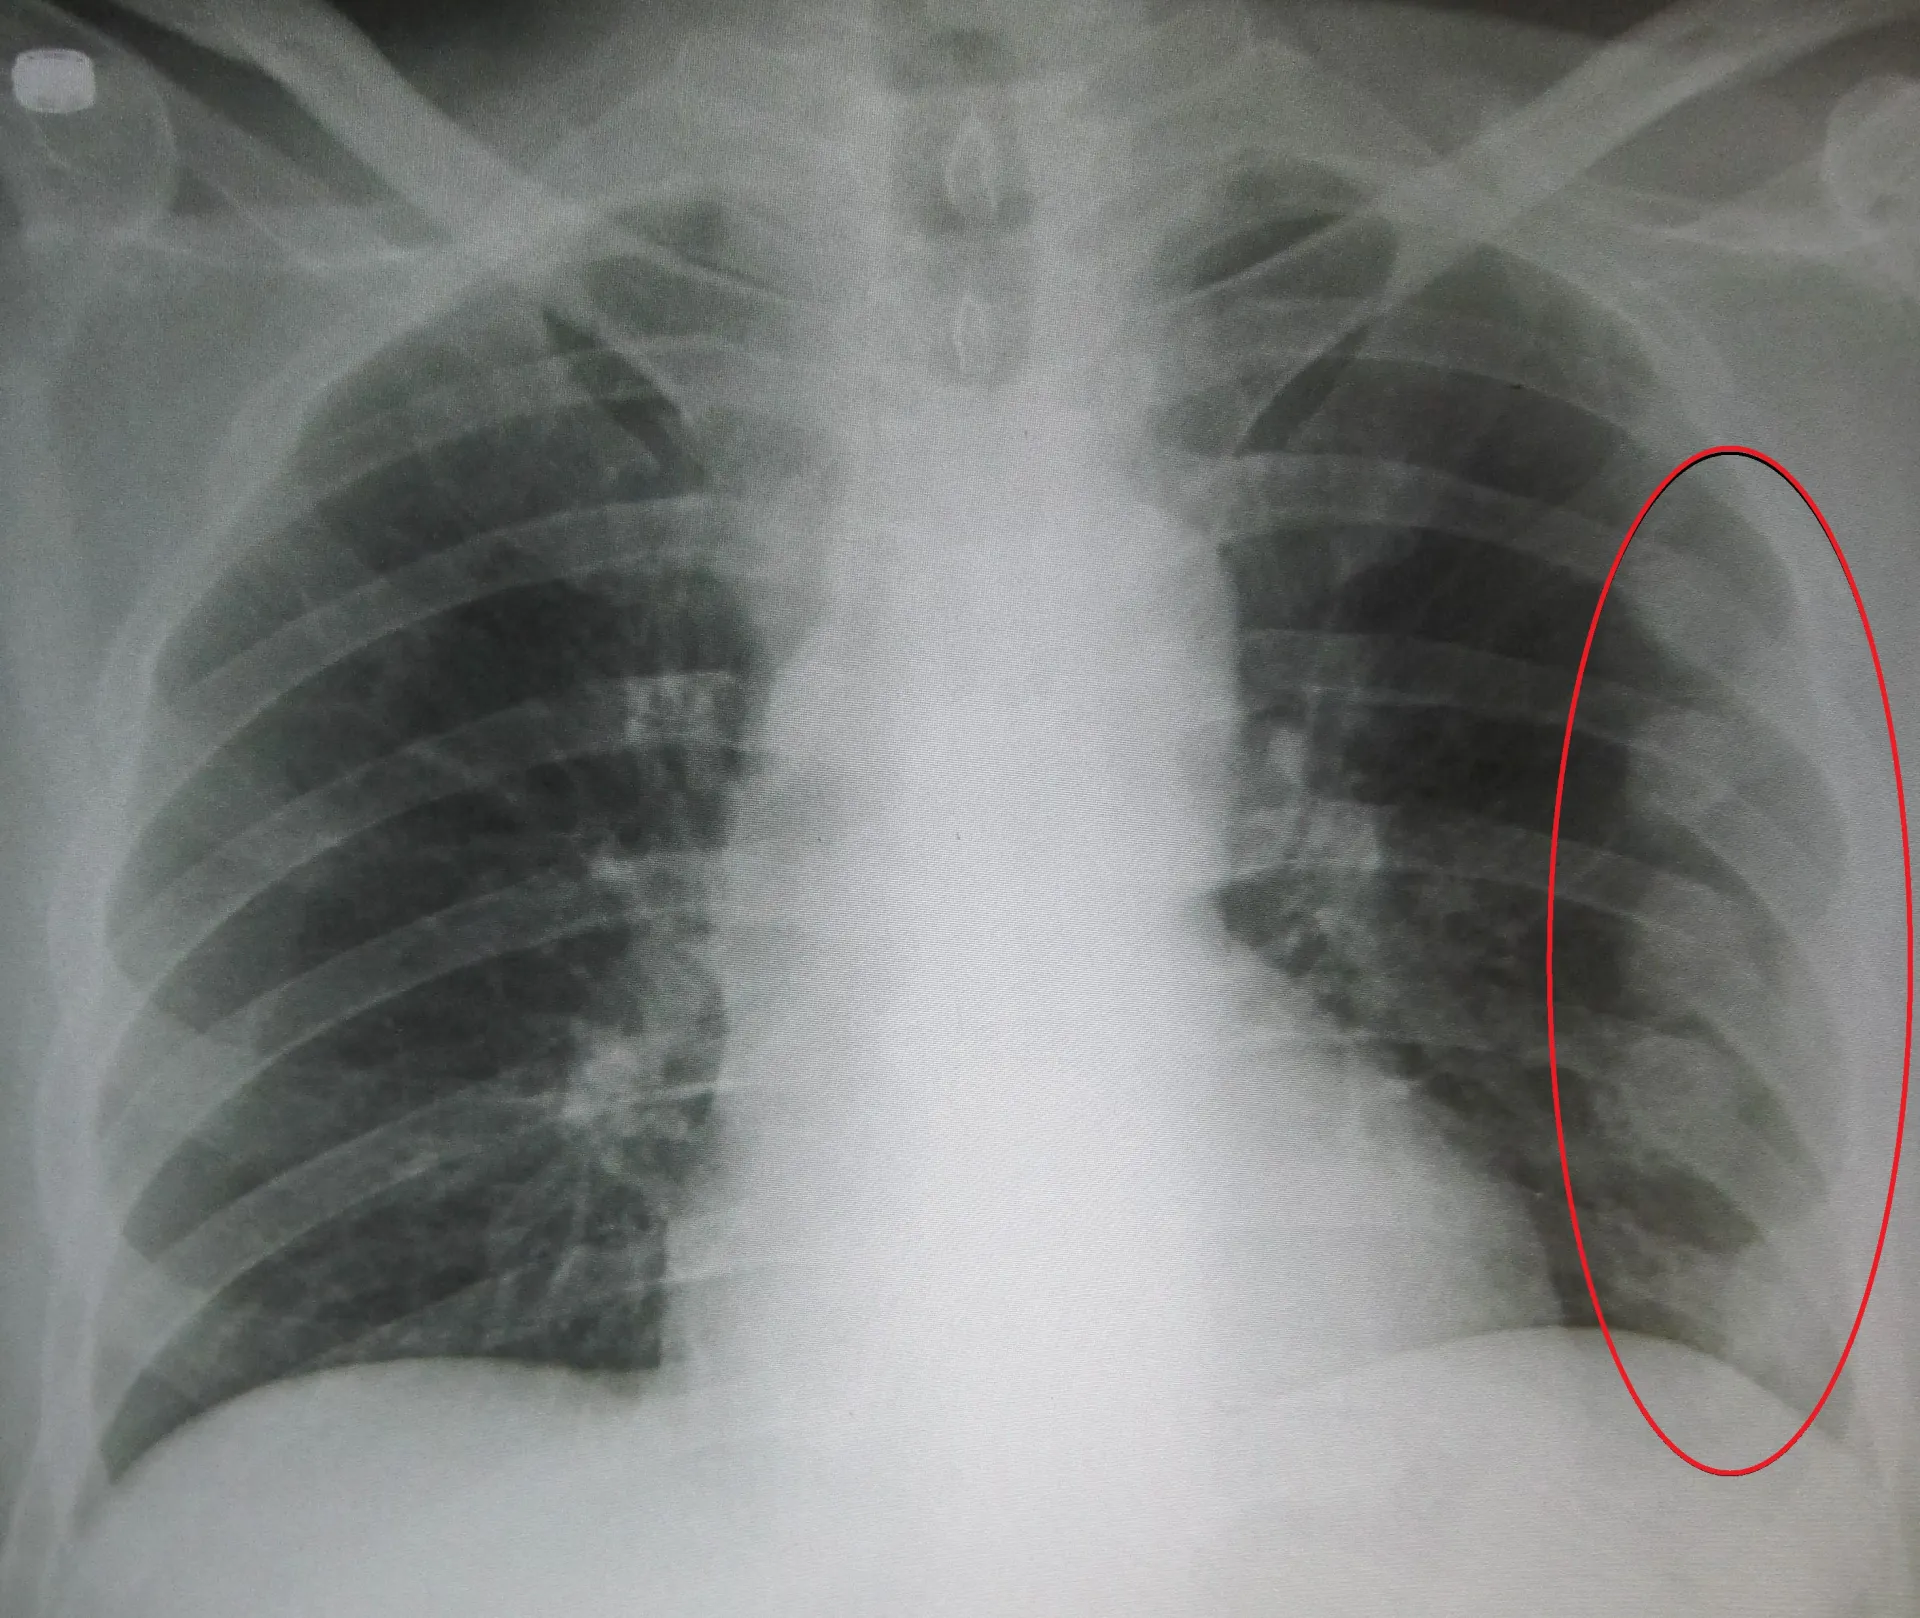

Cụ thể, Trung tâm Kiểm tra sức khỏe của Bệnh viện Nhân dân số 1 ở Hàng Châu, thông báo rằng kết quả chụp CT của phổi cho thấy cô đã gãy xương sườn bên phải và cần phải tới khoa chỉnh hình càng sớm càng tốt. Cô đến bệnh viện ngay sau đó nhưng khẳng định bản thân không hề bị ngã hoặc va đập. Bác sĩ đã đề xuất tiến hành các xét nghiệm thêm để phát hiện tình trạng loãng xương.

Nữ bệnh nhân được phát hiện gãy xương sườn.

Bác sĩ chẩn đoán xương sườn cô bị gãy vì xương đã quá "giòn" do thiếu vitamin D (ảnh minh họa)